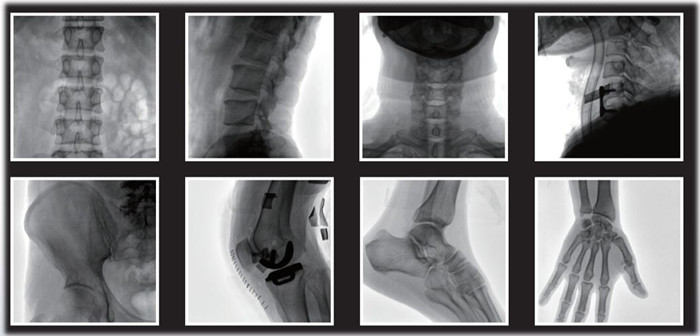

1)小C,骨科手術必備設備,也被稱為骨科小C。作為骨科醫生的眼睛,能在手術中透視實現準確定位,輔助醫生順利、快速、高效完成手術。目前,小C在我國普及率極高,基本上所有二級及以上醫院都標配小C。

小C在骨科的應用是全方位的